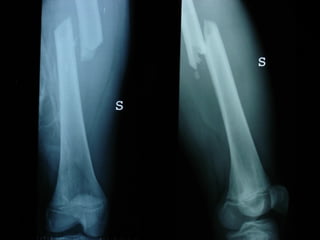

Dal Gennaio 2000 al Febbraio 2006 abbiamo trattato 167 fratture chiuse  con placca percutanea  in 164 pazienti :  27 lesioni diafisarie di gamba, 12 piloni tibiali ,  11 fratture prossimali di tibia, 36 fratture sovracondiloidee di femore, 17 fratture diafisarie di femore, 43 fratture metaepifisarie prossimali di omero, 21 diafisarie d’omero.  156 guarigioni 8 fallimenti

Dal Giugno 2002 al Dicembre 2004 abbiamo trattato 5 fratture esposte: 3 di tibia e 2 di ulna 5 guarigioni

I buoni risultati ottenuti dipendono da 5 punti fondamentali:   una accurata riduzione percutanea della frattura  precise vie di accesso  l’utilizzo della placca che consenta il più lungo braccio di leva possibile il pretensionamento della placca  una sintesi con un ridotto numero di viti

Accurata riduzione percutanea della frattura

Precise vie di accesso

Placche lunghe e pretensionate

Placche lunghe e pretensionate Sintesi con un ridotto numero di viti

2 Insuccessi

Fratture  esposte